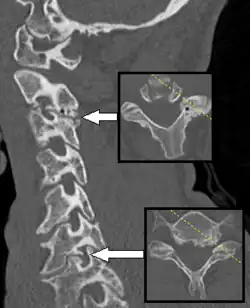

| C5-C6, followed by C6-C7, is the most common location for radiculopathy in the neck. | |